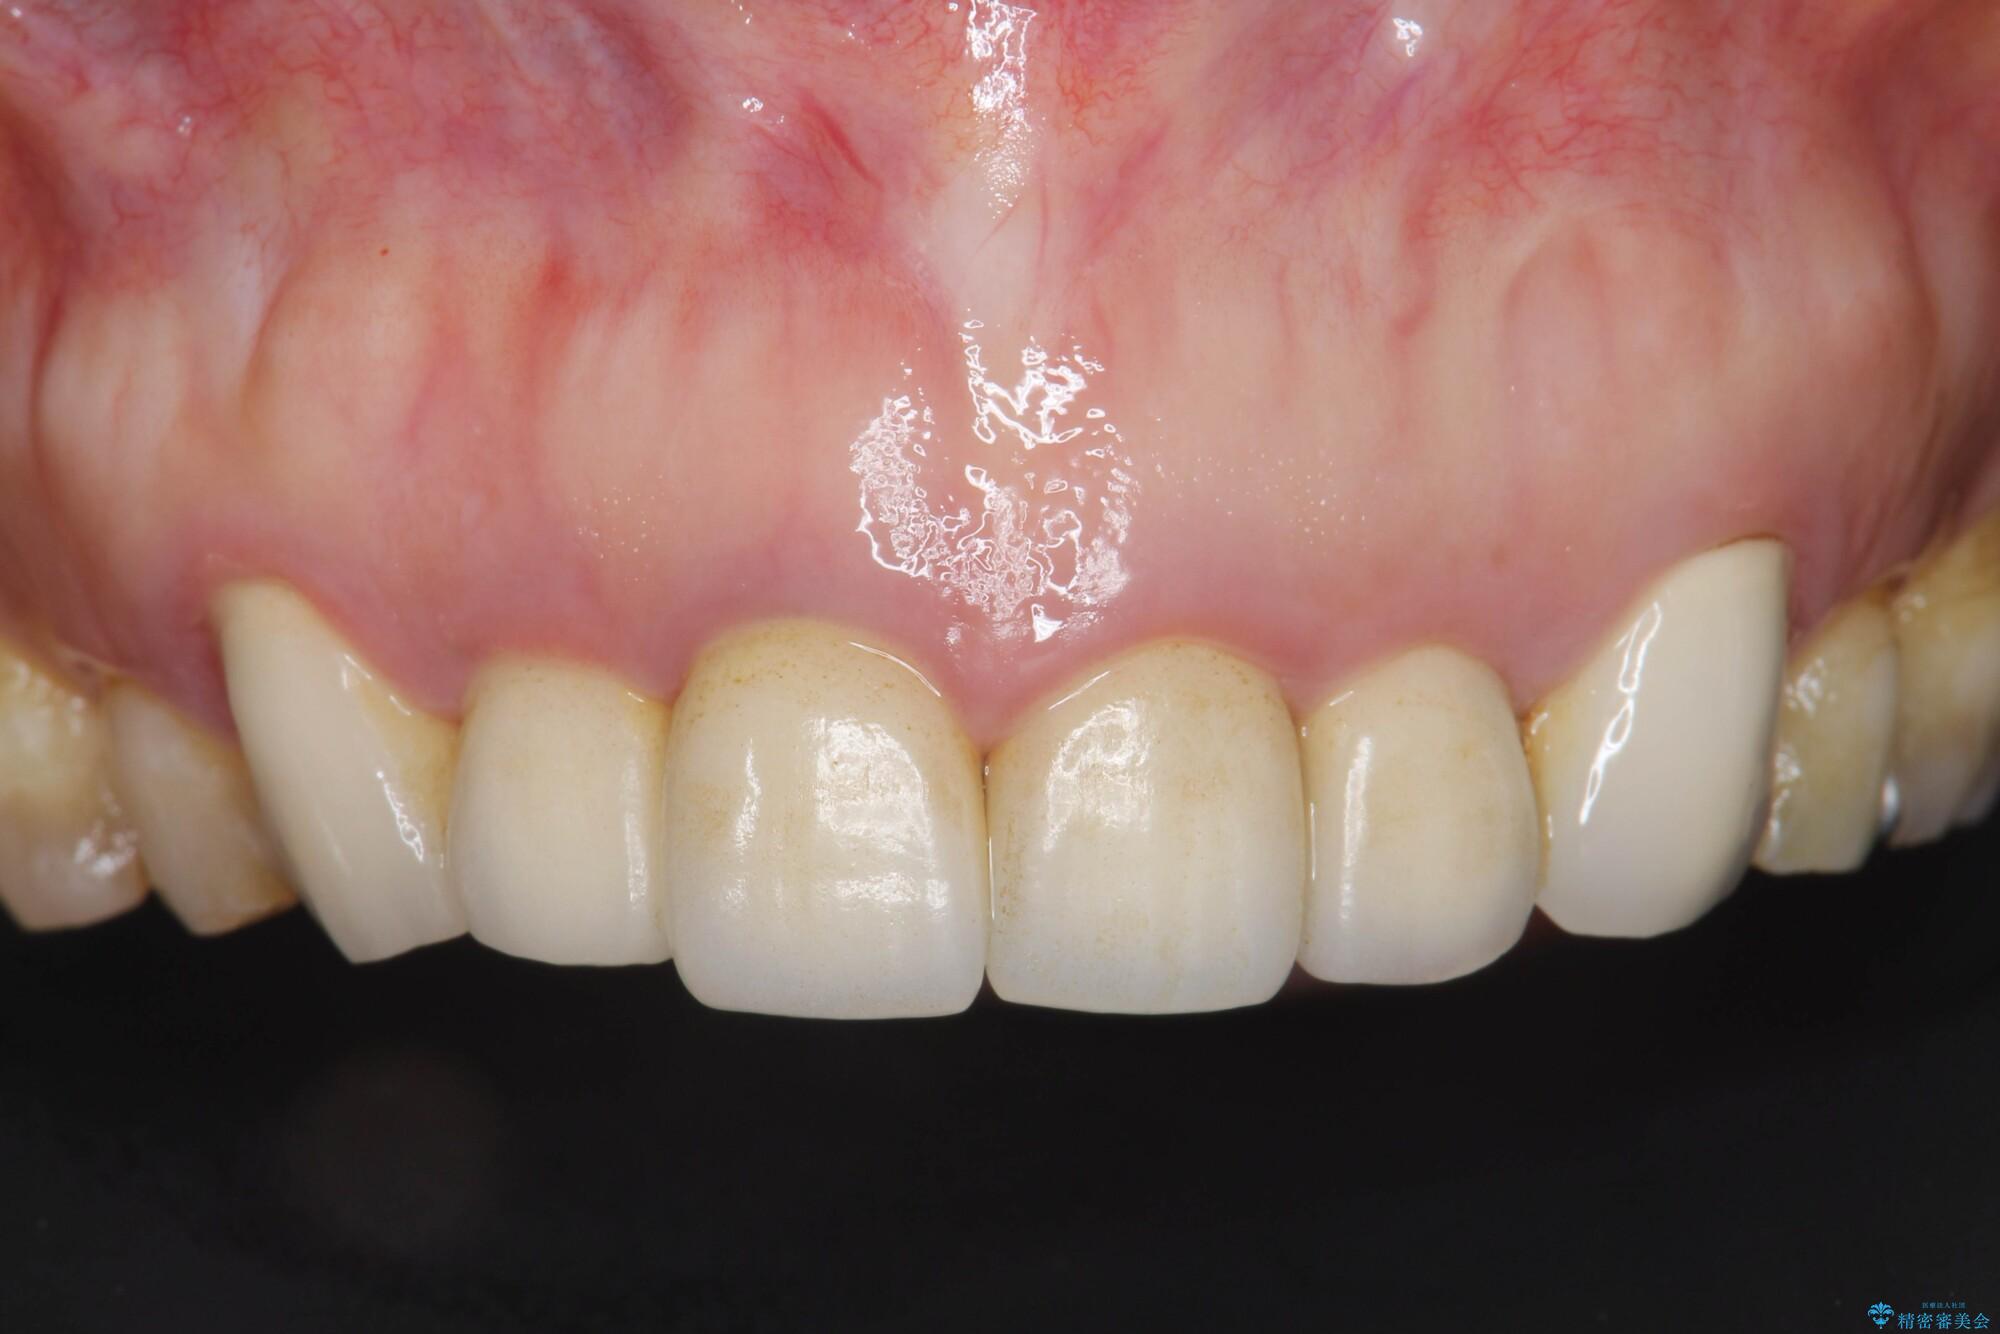

以前に他院で行ったセラミック治療後に、慢性的に歯ぐきからの出血や疼き、違和感がありご相談にいらっしゃった患者様です。

装着されていたセラミックを除去したところ、歯ぐきの奥深くまで歯牙は削られ、歯ぐきの炎症・出血が著しくみられる状態でした。

治療には歯肉を成熟させる期間を含めて約8ヶ月間要しましたが、出血や違和感のない歯ぐきとなり大変ご満足いただけました。